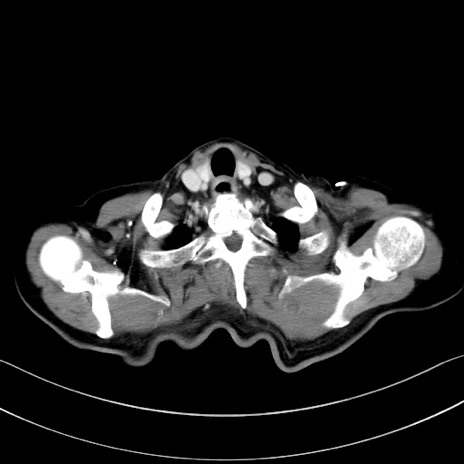

症例28(横断像)

【症例】60歳代男性

【主訴】嘔吐

【現病歴】胃癌にて胃全摘後。食思不振が悪化し、夜中に嘔吐することがある。

【既往歴】胃癌、胃全摘、脾摘、胆摘後

【データ】WBC 5900、CRP 10.56